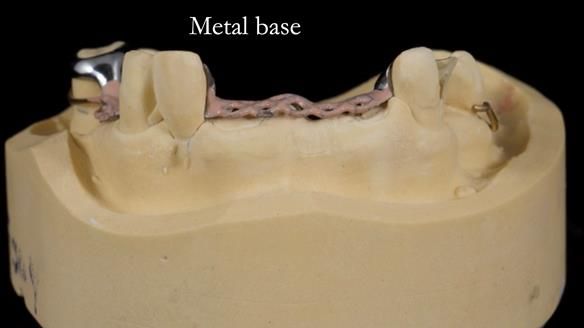

This edition features the case of Edgar, who sought help for a poorly fitting, acrylic-based partial denture that rocked, affected his speech, and caused discomfort. After considering various treatment options, including dental implants, Edgar opted for a metal-based removable partial denture, designed by myself with input from my technician, Rowan Garstang.

Treatment Process: I provided the clinical work while Rowan Garstang delivered the technical aspects. The treatment required fifteen visits to fit and review Edgar.